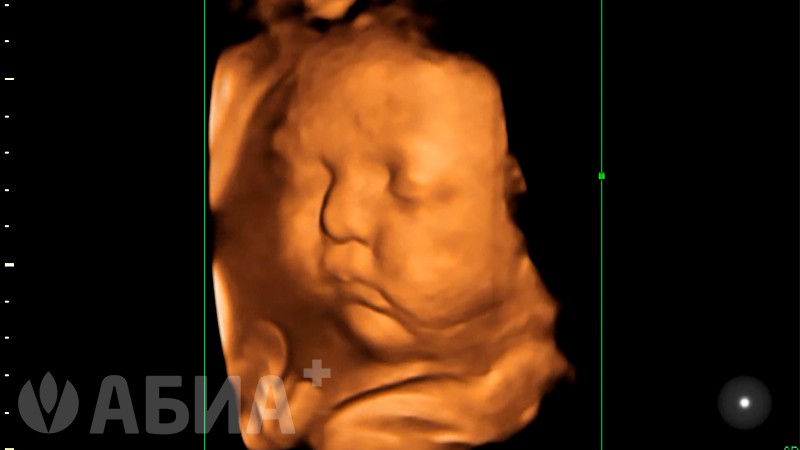

Технология трехмерного сканирования в режиме реального времени (RealTime4D) создает объемную реконструкцию со скоростью до 45 объемных изображений в секунду.

Уже на ранних сроках беременности (11-14 недель) будущая мама получает возможность увидеть кроху целиком, как он двигает маленькими ручками и ножками, машет, кладет ножку на ножку.

Во втором триместре беременности у ребенка активно развивается мимика — именно сейчас вы сможете увидеть его первую улыбку! Малыш сосет пальчик и хмурится, Вы уже можете распознать его ушки, глазки и носик... на небольшом сроке беременности на УЗИ можно увидеть ребенка во весь рост.